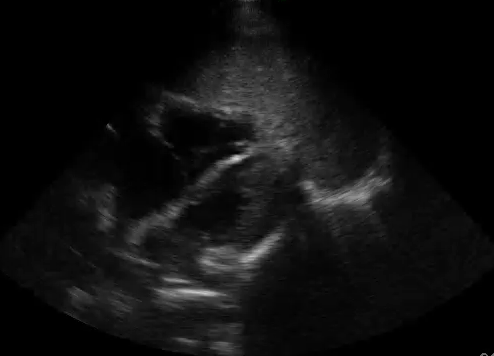

Image Acquisition: Basic Focused Assessed Transthroacic ECHO (FATE) was performed (See videos below).

Image Interpretation: Pericardial effusion was absent yet the right ventricle (RV) was dilated acutely as the RV wall thickness was normal (subcostal).  The systolic D-septum (parasternal) suggested an elevated RV afterload.  Along with the hyperdynamic left ventricle (LV) and normal left atrium (LA), there was likely a flow obstruction between the RV to LA which maybe related to the “lesion” in the RV.

The first and foremost PoCUS interpretation parameter to answer is whether quality of the acquired images is adequate: pristine to unreadable. The images attained were not ideal: the septum of the parasternal long view was not horizontal; the apical 4 view was off axis; and etc… Nevertheless, they sufficed to answer the author’s clinical questions (indications).

“Lesions” and “things” may sometimes be seen in the cardiac chamber as per in this case. It can be thrombus, vegetation – infected or sterile, tumour, or foreign body. There are certain ultrasonographic features that may suggest one differential over another though this differentiation is not the role of PoCUS. In this case, one can only conclude that there is something inside the RV.